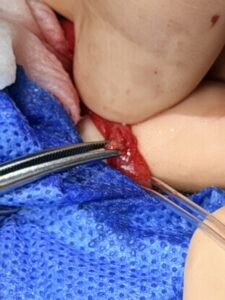

腹腔鏡を用いた尿管切開では、お腹に5㎜サイズの切開を2つと2㎝サイズの切開1つで実施します。

従来の開復で行う方法の1/5程度の切開で実施可能です。

その後尿管を体外へと牽引後尿管切開を行い結石を摘出します。

その切開創から膀胱にもアプローチを行い膀胱結石の摘出も行いました。

術後の傷口はこのくらいです。